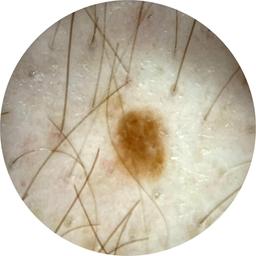

ISIC_8132457

IP_3351570

IL_0861336

anatom_site_1 Lower extremity

anatom_site_general lower extremity

diagnosis_1 Benign

image_type dermoscopic

lesion_id IL_0861336